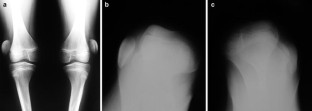

Fig. 1